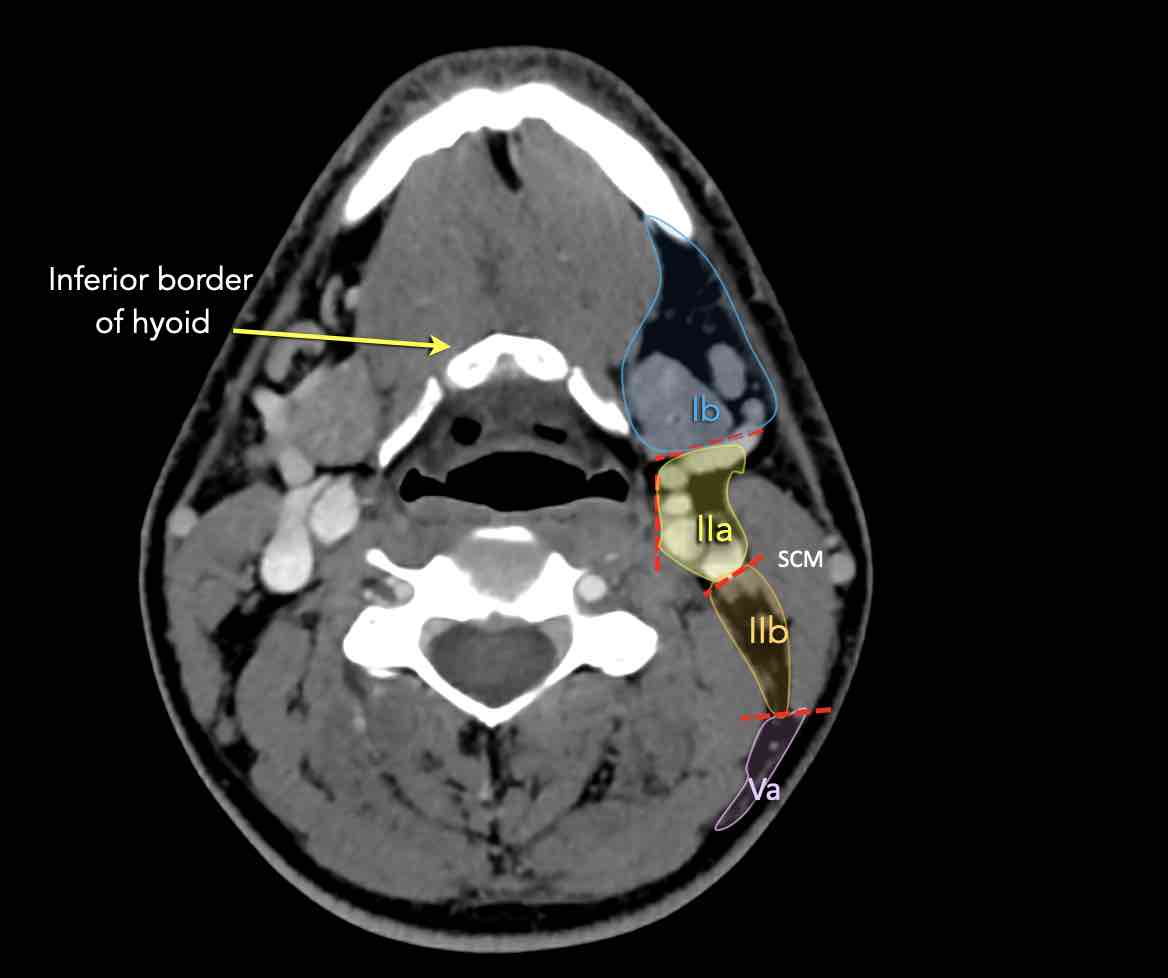

Tầng II có thể được chia thành tầng IIa và tầng IIb bằng cách vẽ một đường tại bờ sau của tĩnh mạch cảnh trong.

Các hạch bạch huyết ở tầng IIa và IIb có nguy cơ chứa di căn từ các ung thư hốc mũi và khoang miệng, vòm hầu, hầu miệng, hạ hầu, thanh quản và các tuyến nước bọt lớn.

V – Tam giác cổ sau và hố thượng đòn

Tầng V chứa các hạch của nhóm tam giác cổ sau nằm ở phía sau cơ ức đòn chũm, xung quanh phần dưới của thần kinh phụ gai sống và các mạch máu cổ ngang.

Các hạch bạch huyết ở tầng V thường liên quan nhất đến các ung thư nguyên phát của vòm hầu, hầu miệng, các cấu trúc da vùng da đầu phía sau và tuyến giáp.